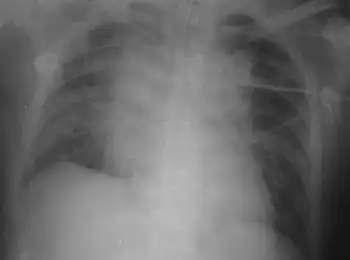

Chest X-rays and X-ray computed tomography (CT) can reveal areas of opacity (seen as white), indicating consolidation.[13] CAP does not always appear on x-rays, sometimes because the disease is in its initial stages or involves a part of the lung not clearly visible on x-ray. In some cases, chest CT can reveal pneumonia not seen on x-rays. However, congestive heart failure or other types of lung damage can mimic CAP on x-ray.[15]

When signs of pneumonia are discovered during evaluation, chest X-rays and examination of the blood and sputum for infectious microorganisms may be done to support a diagnosis of CAP. The diagnostic tools employed will depend on the severity of illness, local practices and concern about complications of the infection. All patients with CAP should have their blood oxygen monitored with pulse oximetry. In some cases, arterial blood gas analysis may be required to determine the amount of oxygen in the blood. A complete blood count (CBC) may reveal extra white blood cells, indicating infection.